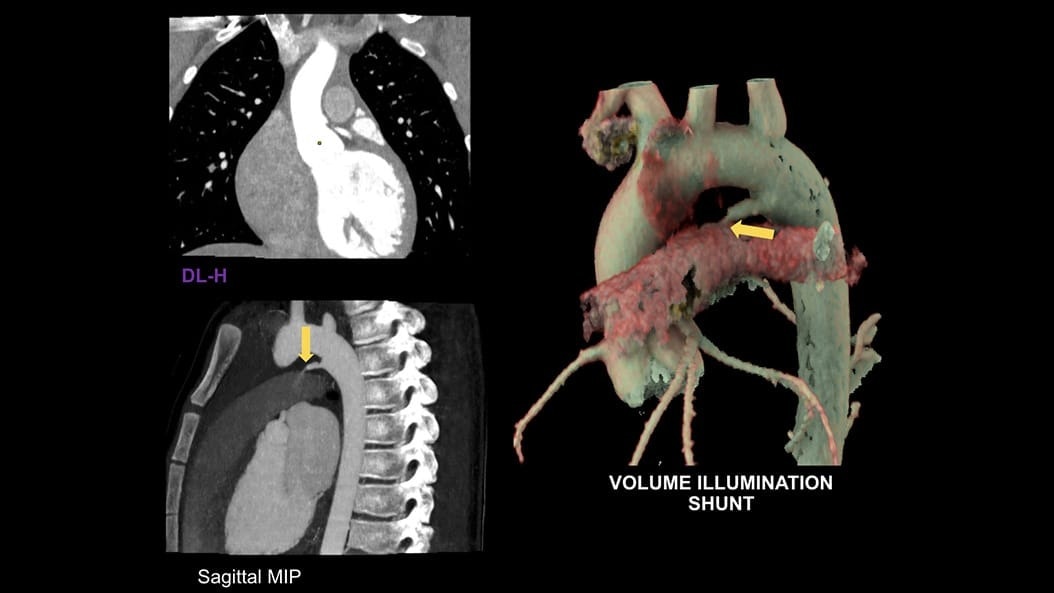

CT-Guided Interventional Care

Since becoming an important step in the patient care pathway and heart care guidelines, CT images are an invaluable tool in the cath lab, guiding procedures for precise personalized care.